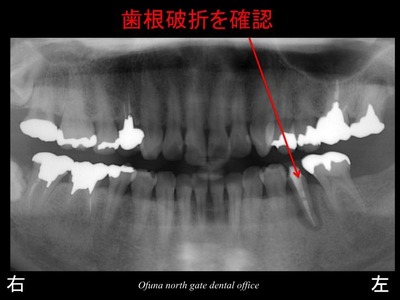

診査の結果、歯根破折 と診断されました。

先週の症例も歯根破折 でしたが、本当によくあることなのです。

先ほどの症例と同様に歯根破折 していました。

以下が初診時です。

下顎左側の奥から2番目の歯の被せ物が取れたとのことで来院されました。

歯肉の中までおよぶ深い虫歯となっていました。

虫歯となっている歯の手前は、だいぶ前に抜歯されたそうです。

これも保存が難しいため、抜歯となりました。